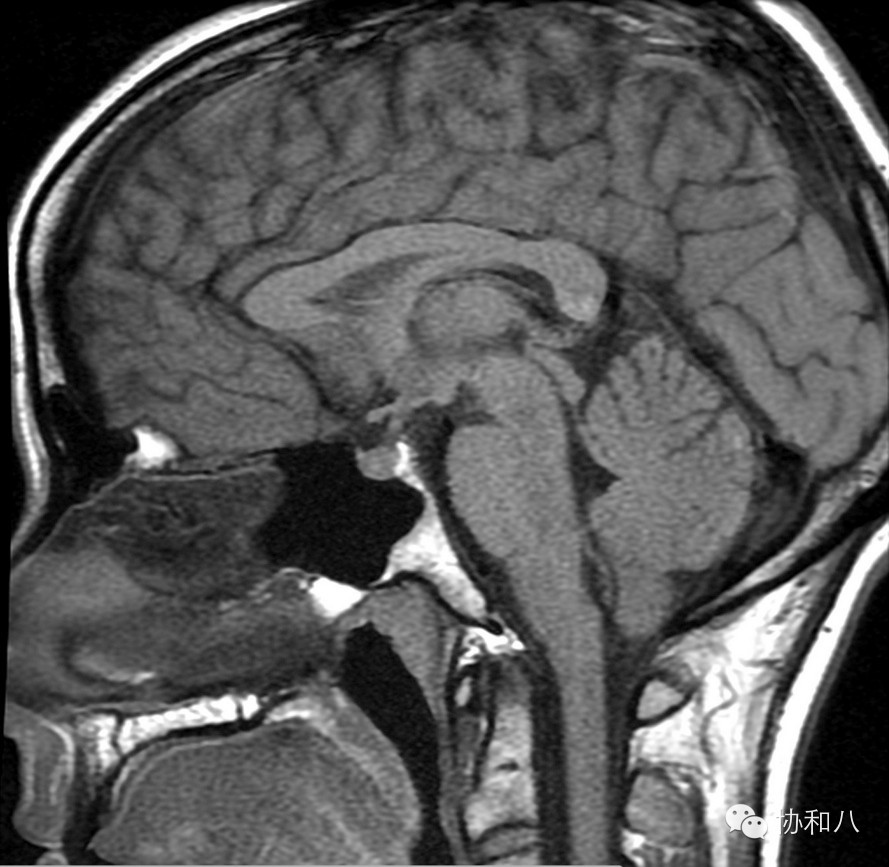

下图:(冠状位MRI T1WI)鞍上可见混杂信号占位,其中可见T1WI上明显高信号,同时右侧外侧裂可见数个结节状明显高信号,符合鞍区畸胎瘤破裂表现。